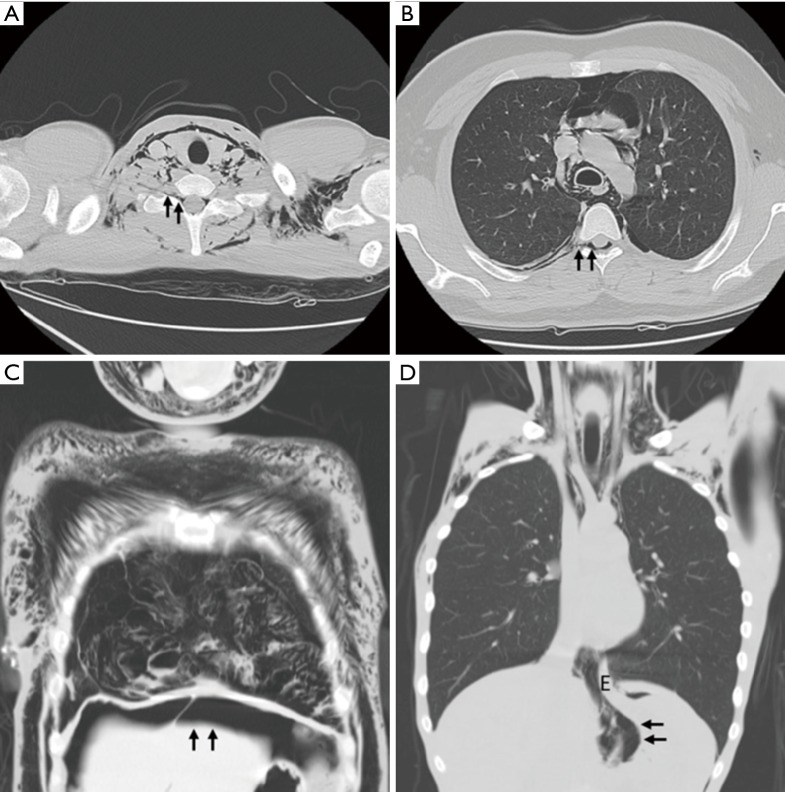

Figure 1.

Spontaneous pneumomediastinum with concomitant extrathoracic air leaks. (A) Patient 1 disclosed neck and chest wall subcutaneous emphysema, pneumomediastinum, and pneumorrhachis originated from deep cervical fascial planes (arrows); (B) patient 2 revealed pneumomediastinum with pneumorrhachis, which resulted from adjacent neural foramen (arrows); (C) patient 3 showed massive subcutaneous and mediastinal emphysema with concomitant pneumoperitoneum (arrows); (D) patient 4 demonstrated pneumomediastinum and air dissection along periesophageal fascial planes to cause pneumoretroperitoneum (arrows). E, esophagus.

In the recent 2 years at our institution, a preliminary investigation for SPM was initiated retrospectively based on the authors’ classification. Surprisingly, we found that several cases of severe type of SPM exhibit additional epidural air, which is also known as pneumorrhachis (Figure 1A,B). Spontaneous pneumorrhachis is a rare condition and occasionally correlates with SPM. It is hypothesized to originate from air leak spreading through the posterior mediastinum into the epidural space via the cervical fascia planes or neural foramen (7). Owing to its scarcity in nature, there is no established incidence of pneumorrhachis associated with SPM except for only one published study revealing 4 out of 42 cases (9.5%) of SPM as well as extensive subcutaneous emphysema, suggesting that in SPM, pneumorrhachis is uncommon but not extraordinary (8).

With the continuing advancement in imaging studies and frequent adoption of chest computed tomography in cases of SPM, pneumorrhachis may be increasingly detected. In spite of its benign and self-limiting entity, we would like to reclassify the degree of severity in SPM, encompassing the most severe type with concomitant pneumorrhachis and/or other extrathoracic air leak such as pneumoperitoneum and pneumoretroperitoneum (Figure 1C,D).